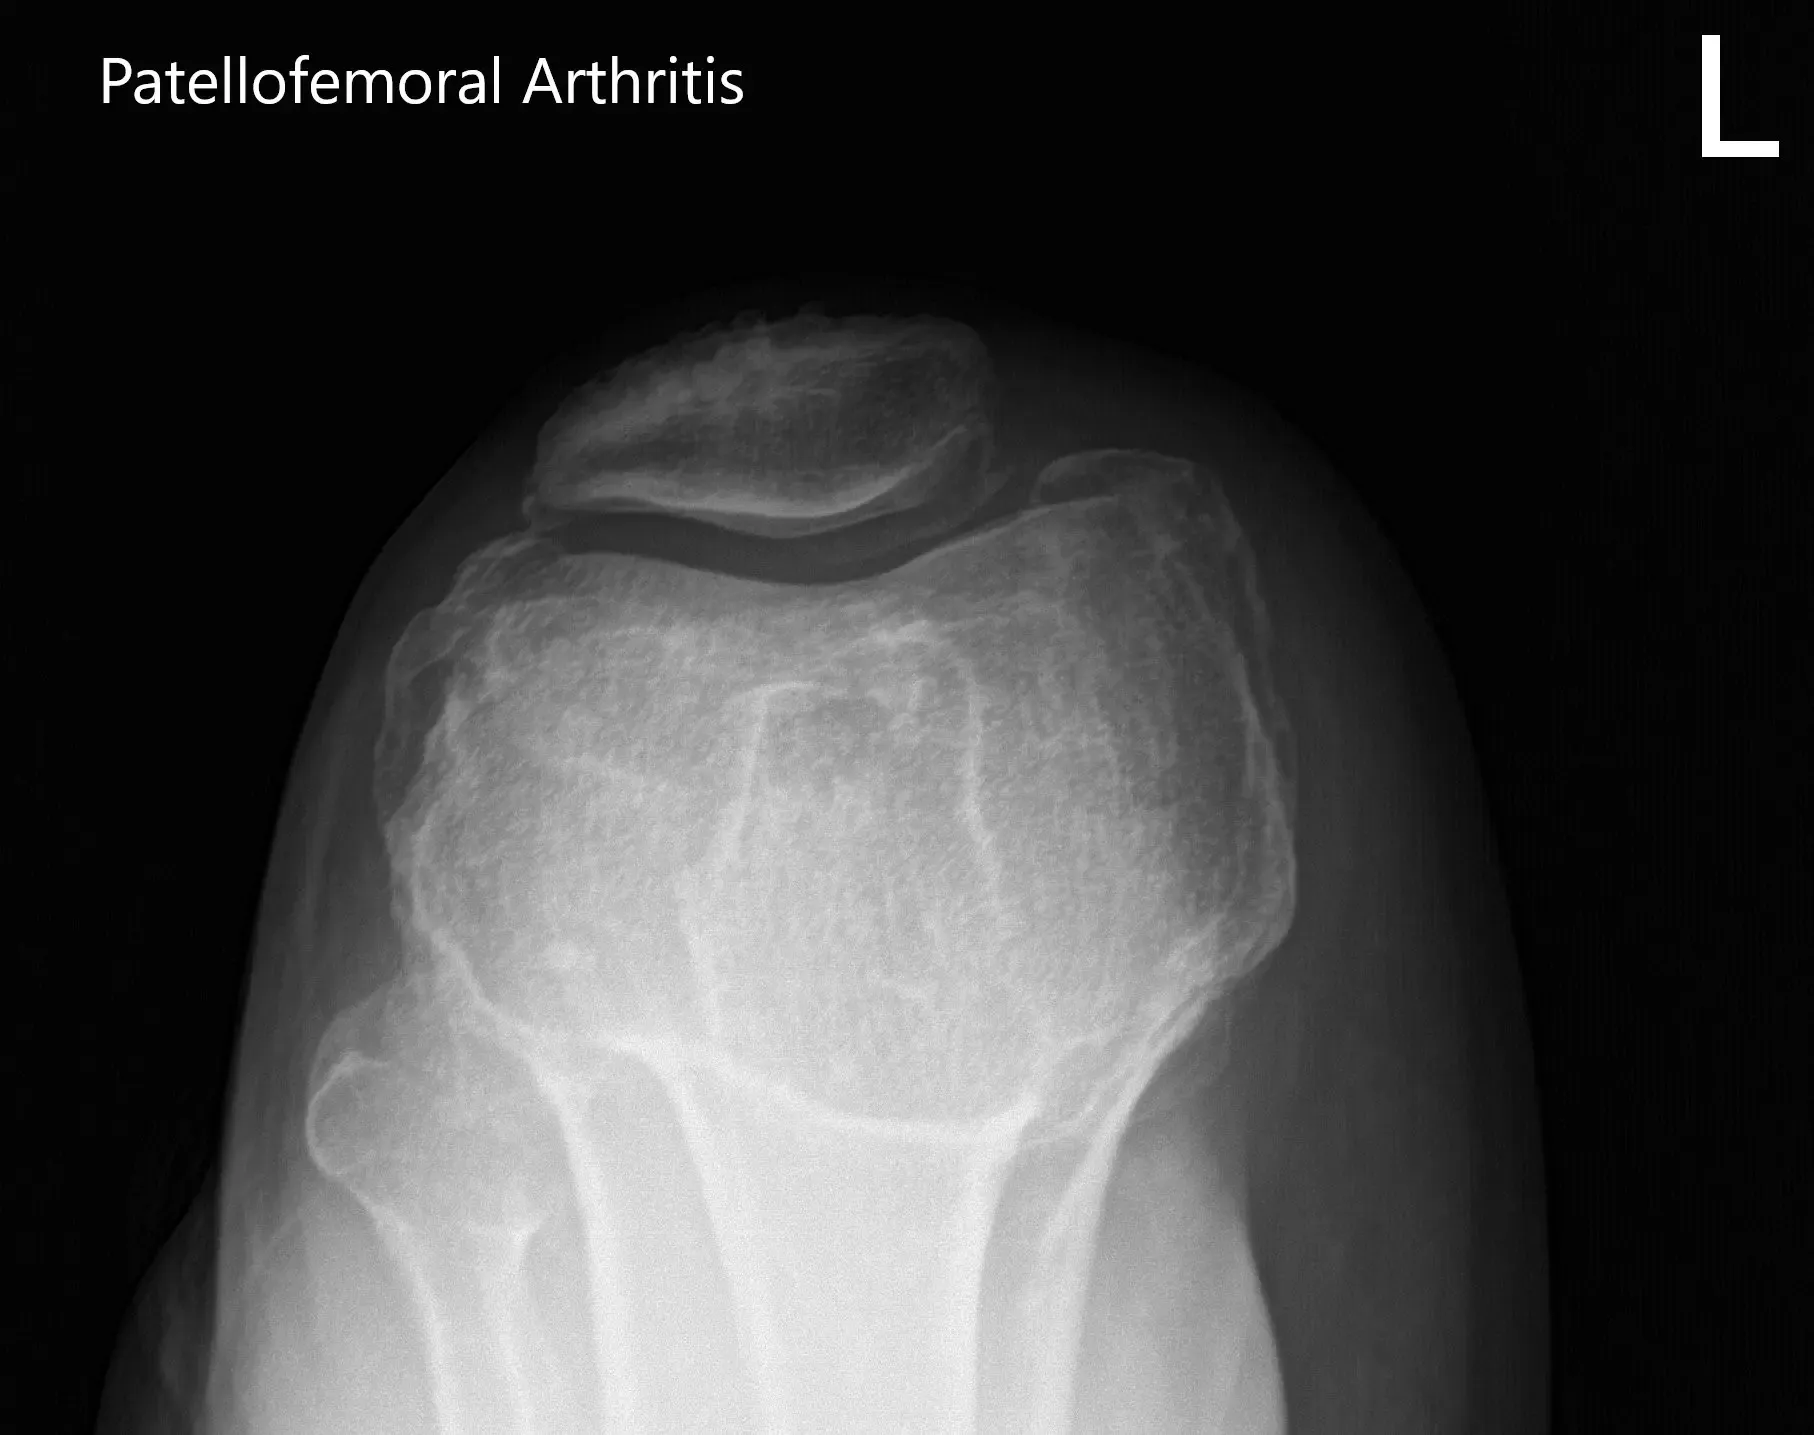

There was no distal neurological deficit and the bilateral pulses were good volume and comparable. Imaging studies revealed severe tricompartmental osteoarthritis of the left knee. Considering the patient’s lifestyle limiting knee pain, she was advised customized left knee total replacement. Risks, benefits, and alternatives were discussed with her at length. She agreed with the plan.

Preoperative X-ray of the left knee showing AP, lateral and merchant views